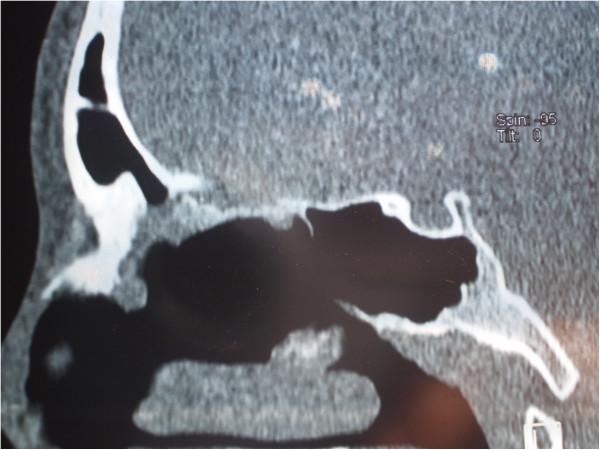

We report an unusual case of middle turbinate osteoblastoma associated with right-sided nasal obstruction and severe headache in a 14-year-old Caucasian girl. The tumor involved the right middle turbinate, complete anterior and incomplete posterior ethmoidal cells, and the frontal sinus ostium. Cribriform lamina was, in the most part, consumed by the tumor growth, while the skull base was mostly of normal bone structure.

我们报告一例不寻常的右侧中鼻甲骨母细胞瘤病例,该病例发生在一名14岁的白种女孩身上,伴有右侧鼻塞和严重头痛。肿瘤累及右侧中鼻甲、完整的前筛窦和不完整的后筛窦以及额窦开口。筛状板大部分被肿瘤生长所破坏,而颅底大部分骨质结构正常。